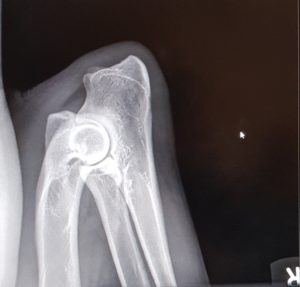

Endnu 2 hunde er blevet bedømt af DKK og fundet HD, AD og OCD frie, vi er så glade og stolte!